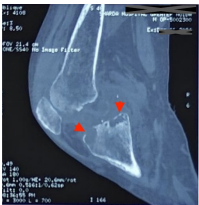

Acute Shoulder Injury Following Tdap Vaccination: A Case Report on SIRVA and the Importance of Proper Injection Technique

Kate Isoken Obayagbona, Weiwei Zhao, Ajibola Mobolaji Arowona, Joshua Olufisayo Odeyemi, Lubna Mirza

Abstract 39 | PDF Downloads 37 EPUB Downloads 37

Page 1262-1265